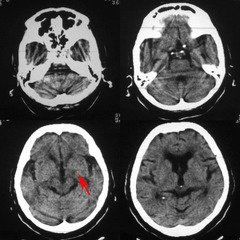

腦腔梗在臨床上較為常見,就是通常所說的腔隙性腦梗塞,屬於腦梗塞(腦血栓、腦栓塞、腔隙性腦梗塞、多發性腦梗塞、短暫性腦缺血發作)的一種特殊類型,多發生在基底節區。是在高血壓、動脈梗化的基礎上,腦深部的微小動脈發生閉塞,引起腦組織缺血性軟化病變。其病變範圍一般為2-20毫米,其中以2-4毫米者最為多見。臨床上患者多無明顯症狀,約有3/4的患者無病灶性神經損害症狀,或僅有輕微注意力不集中、記憶力下降、輕度頭痛頭昏、眩暈、反應遲鈍等症狀。部分多發性腦腔梗,可影響腦功能,導致智力進行性衰退,最後導致腦血管性痴呆。該病的診斷主要為CT或MRI檢查,

對於“腔梗”的形成原因大多認為由高血壓所致的腦內細小動脈硬化,進而引起深部腦組織點狀缺血、壞死、液化並由吞噬細胞移走而形成一個小孔隙,即是CT片上所見的小低密度影。中年以上(一般指45歲以上)有高血壓病的,如果再有糖尿病、高血脂等腦血管病的危險因素,出現這樣的小“腔梗”是很多的。